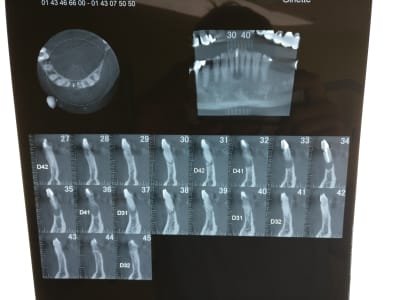

Ci joint le cône beam

Mais surtout que pensez vous de ce qu'on voit sur les coupes 31 et 38? Morceaux de racines ? lors de l'exo faut les virer aussi? voir même extraire 41 et 32?

En fait, ce qui m'a induit en erreur, c'est la coupe 15 du doc 3, je ne comprends pas son orientation. L'image est très différente des coupes du doc 4.

(elle est en rotation de manière importante la 31?)

D'ailleurs, c'est une 41.

Je pense que j'ai compris, je pense que tu devrais trouver le second en linguo distal.

Pour les apexs (?), la lésion ne semble pas centrée dessus. Si résection, peut-être devras tu alors les virer et faire 2 endos supplémentaires...

Recherche ce canal supplémentaire avant. (disto lingual!)

A la base je pense qu'il y avait un second canal en lingual. Regarde les coupes horizontales tu devrais le trouver ou au moins l'imaginer. Sur les coupes sagittales, le canal que tu as obture est deporte en vestibulaire, c'est une bonne indication. Sur la retro tu vois bien les deux racines de l'incisive latérale, tu trouves en general 2 canaux sur la centrale dans ce cas la.